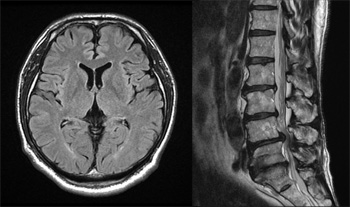

MRIは強力な磁石による磁場と電波を使って、患者様の体内を観察し病気を診断する検査法です。人体を構成する原子核は、磁気と共鳴して信号を発生します(核磁気共鳴現象)。この信号をとらえ画像化することにより、人体内部の構造を観察します。

MRIでは核磁気共鳴現象に特有のパラメータを、色々な具合に調整して撮影することができます。この調整により、まるで様々な調味料の配合をした料理を作るように、正常な部分と異常な部分を区別しやすい画像や、造影剤を使用せずに血液の流れを見る画像など、多種多様な画像を得ることができます。縦、横、斜めなど人体の任意の断面を画像化でき、3次元的な画像の取得も可能です。また、単なる構造の把握のみならず、最近では機能画像を得ることもできるようになっています。X線を使用しないので放射線による被ばくもありません。

千葉大学医学部附属病院では3テスラが2台、1.5テスラが3台の超伝導磁場装置が稼動しています。特に3テスラ装置では高い信号雑音比を生かした高分解能撮影が達成され、指の関節のような微細な構造の評価に有用です。また、撮影方法の進歩によって高速撮影化が進んでおり、肝臓のように呼吸による動きの強い臓器でも、1回の息止めで1回の撮影を完了することが可能です。さらに、全国に先駆けた特殊な撮影方法を用いることによって、従来は評価困難とされていた腱や靭帯、神経を視覚化することができ、これらの損傷はある程度評価できるようになってきました。その他様々な臨床研究を行っていて、今後の医療の発展に貢献するように日々努力しています。